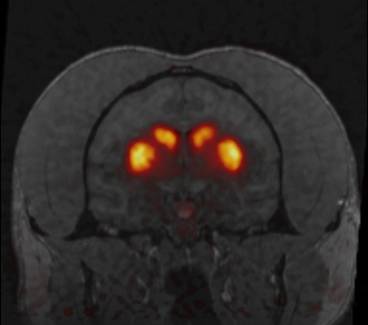

The human and non-human primates participate in behavioral testing and brain imaging (like MRI and PET scans) to assess how brain structure and function changes with methamphetamine dependence. Crucially, however, these methods do not allow us to directly monitor the molecules themselves that cause brain dysfunction in addiction. For that, we must undertake studies of brain matter collected from rats or monkeys after euthanasia (death produced by painless administration of an anesthetic).